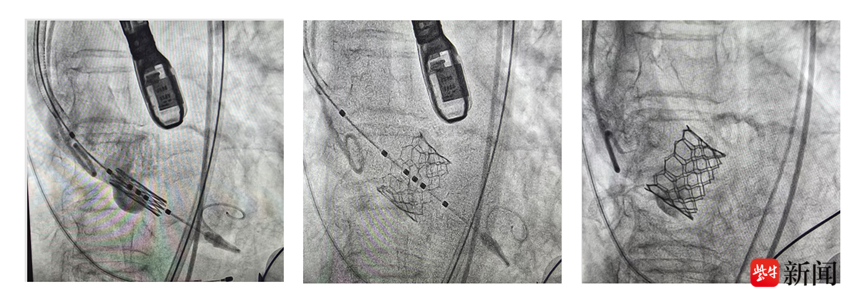

影像图

TAVI术中通过股动脉送入介入导管,首先采用球囊对患者重度狭窄的主动脉瓣膜进行预扩张,后将人工主动脉瓣膜送到拟释放位置,精确定位,人工瓣膜顺利释放,替换了原来重度狭窄伴钙化的瓣膜,术中经食道超声确认新的瓣膜位置准确、开放自如,患者主动脉瓣的功能得以恢复,手术成功。